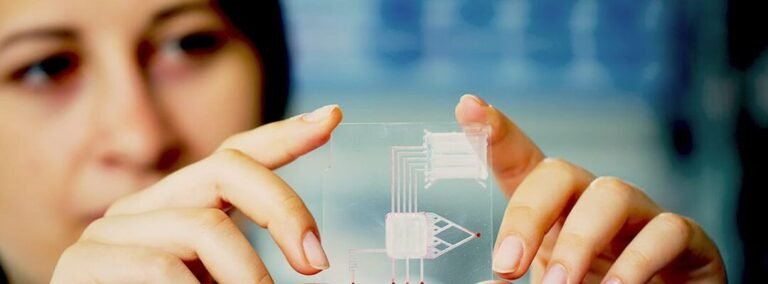

Los avances en nanotecnología han abierto nuevas posibilidades en el campo médico, destacando especialmente los . Estas...

El representa una innovadora frontera en la biotecnología médica, ofreciendo una alternativa accesible y sostenible a los...